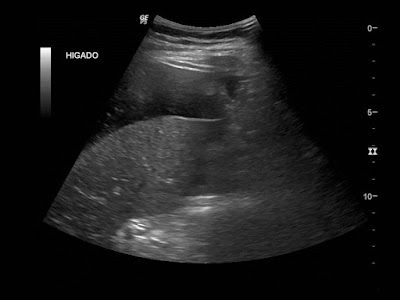

Dolor en hipocondrio derecho

Femenina de 31 años